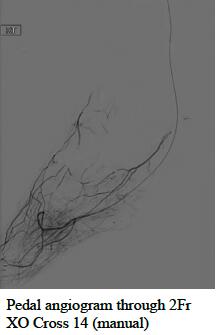

“The XO Cross devices deliver unique performance and control that make them an excellent tool for crossing above- and below-the-knee lesions,” said Dr. Jihad Mustapha, interventional cardiologist at Advanced Cardiac & Vascular Center in Grand Rapids, Michigan, USA. “The non-tapered XO Cross shaft, lubricious coating, low crossing profile, and 1:1 torque response will be critical for workhorse performance and reducing the need for wire escalation techniques in CLI cases.”

The unique XO Cross platform includes a metal-alloy exoskeleton, non-tapered shaft, proprietary hydrophilic lubricious coating, and large inner lumen for improved 1:1 torque, low-profile, pushability, tracking, crossing, fatigue-resistance, and angiography. XO Cross microcatheters have been safely and successfully used in challenging peripheral lesions above-the- including but not limited to above-the-knee and below-the-knee CTOs from contralateral femoral, antegrade femoral, and retrograde pedal access.

This 510k clearance includes new 2Fr XO Cross 14 Microcatheters, 2.6Fr XO Cross 18 Microcatheters, and 3.8Fr XO Cross 35 Support Catheters for use with standard 0.014”, 0.018”, and 0.035” guidewires in 90cm, 135cm, 150cm, and 175cm working lengths. The shorter 90cm devices support retrograde pedal and antegrade femoral access while the longer 175cm devices were designed specifically for radial access to peripheral use.